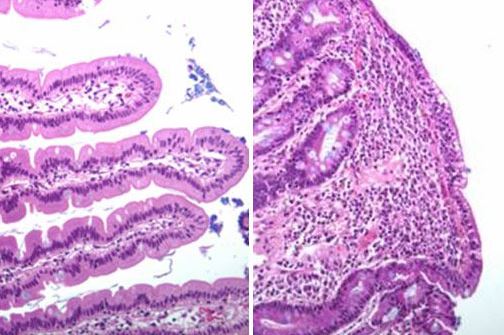

In the case of celiac disease, the T cells think that gluten is a virus or bacteria. Tissue and enzymes are attacked, the villi become damaged and the patient can suffer weight loss, reduced absorption of nutrients and stomach pains.

Left: Healthy duodenum. Right: Duodenum showing villi damaged by celiac disease. Photo: UiO.